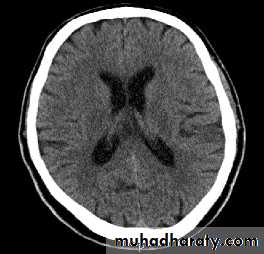

Hydrocephalus

• An abnormal increase in the volume of• CSF

• Symptoms: sleep changes, spastic

• paresis, papilledema, bulging of skull in

• young, seizures, cranial nerve deficits,

• depression.